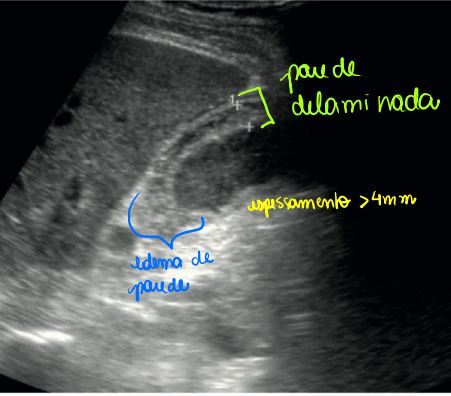

Como é o USG clássico da colecistite?

A

Espessamento (> 4 mm); edema de parede;

Murphy ultrassonográfi co; cálculo impactado;

parede delaminada; edema e líquido

perivesicular.

OBS: TC pode ajudar a avaliar complicações e DG diferenciais em caso de dúvidas!

Se USG»_space; TC»_space; ainda tem dúvidas?

COLECISTOGRAFIA (padrão ouro) - positivo se não tiver enchimento da vesícula.

How well did you know this?